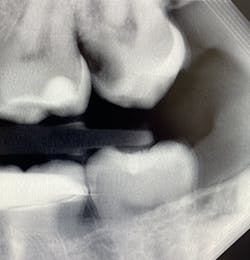

I see more complications and pathologies when using 3D tomosynthesis than I ever did with my old 2D images (figure 4). I can treat more because I can see more bone loss, interproximal caries, fractures, resorptions, abscesses, and more (figure 5).

Fortunately, 3D intraoral tomosynthesis found its way into the dental field. Based on the findings from a study out of the University of North Carolina, dentists who use 3D tomosynthesis for intraoral x-rays can detect approximately 36% more caries (figures 8 and 9).1 That’s tremendous!